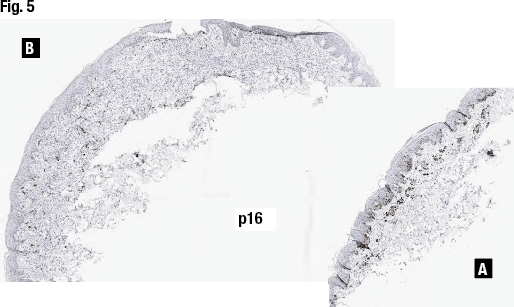

When she and her colleagues looked at the MART-1/Ki67 stain (Fig. 4), the nevoid cells showed no or low proliferative rate, Dr. Aung said, though the epithelioid atypical cell in fragment B showed a relatively high proliferation rate. p16 staining (Fig. 5) showed “complete loss in the atypical cells and the retained nuclear expression pattern in the nevoid cells.”

FISH results were positive, Dr. Aung said, with homozygous loss of CDKN2A (p16/9p21) in 35.3 percent of the atypical epithelioid cells (cutoff: >29 percent).

It is a case of Spitzoid melanoma with associated nevus because of biphenotypic morphology with p16 loss in the epithelioid atypical cells, cytologic atypia, presence of mitotic figures with a high Ki67 proliferative rate, and homozygous loss of 9p21 by FISH, she said.